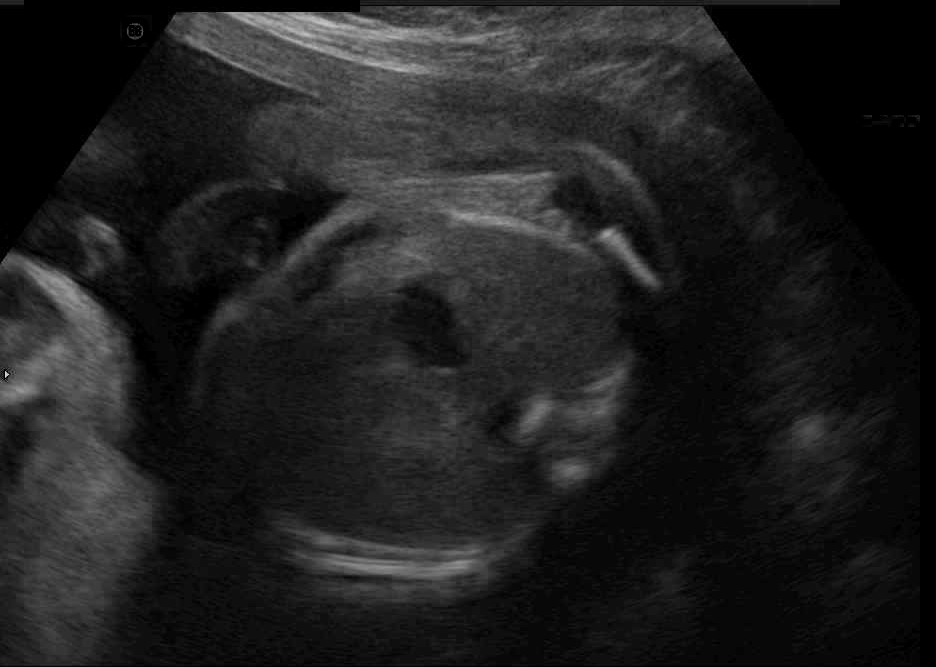

Real in-vivo images. 22 ultrasound sequences were collected using a GE Voluson E8 machine during standard fetal screening exams of 8 patients. Each sequence is several seconds long. We extracted all 4427 frames and resize them to , see Fig. 2 for some examples. The resulting image set was randomly split into training-validation-test sets by a 80-10-10% ratio.